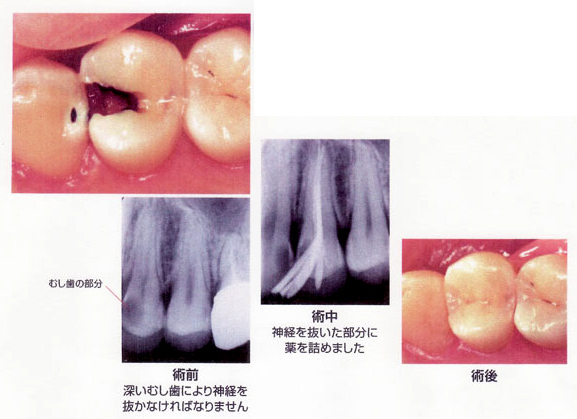

CASE 03 大きく神経まで到達しているむし歯

【病態】

【治療(過程)】